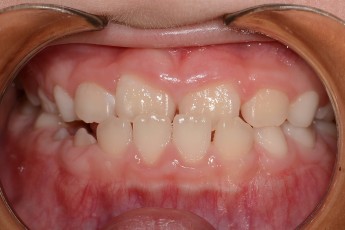

- 덧니교정

Before

After